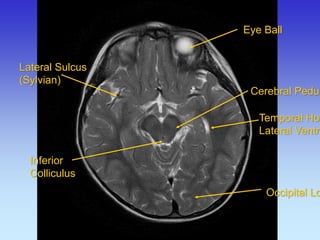

Eye Ball

Cerebral Peduncle

Temporal Horn Lateral Ventricle

Occipital Lobe

Lateral Sulcus (Sylvian)

Inferior Colliculus